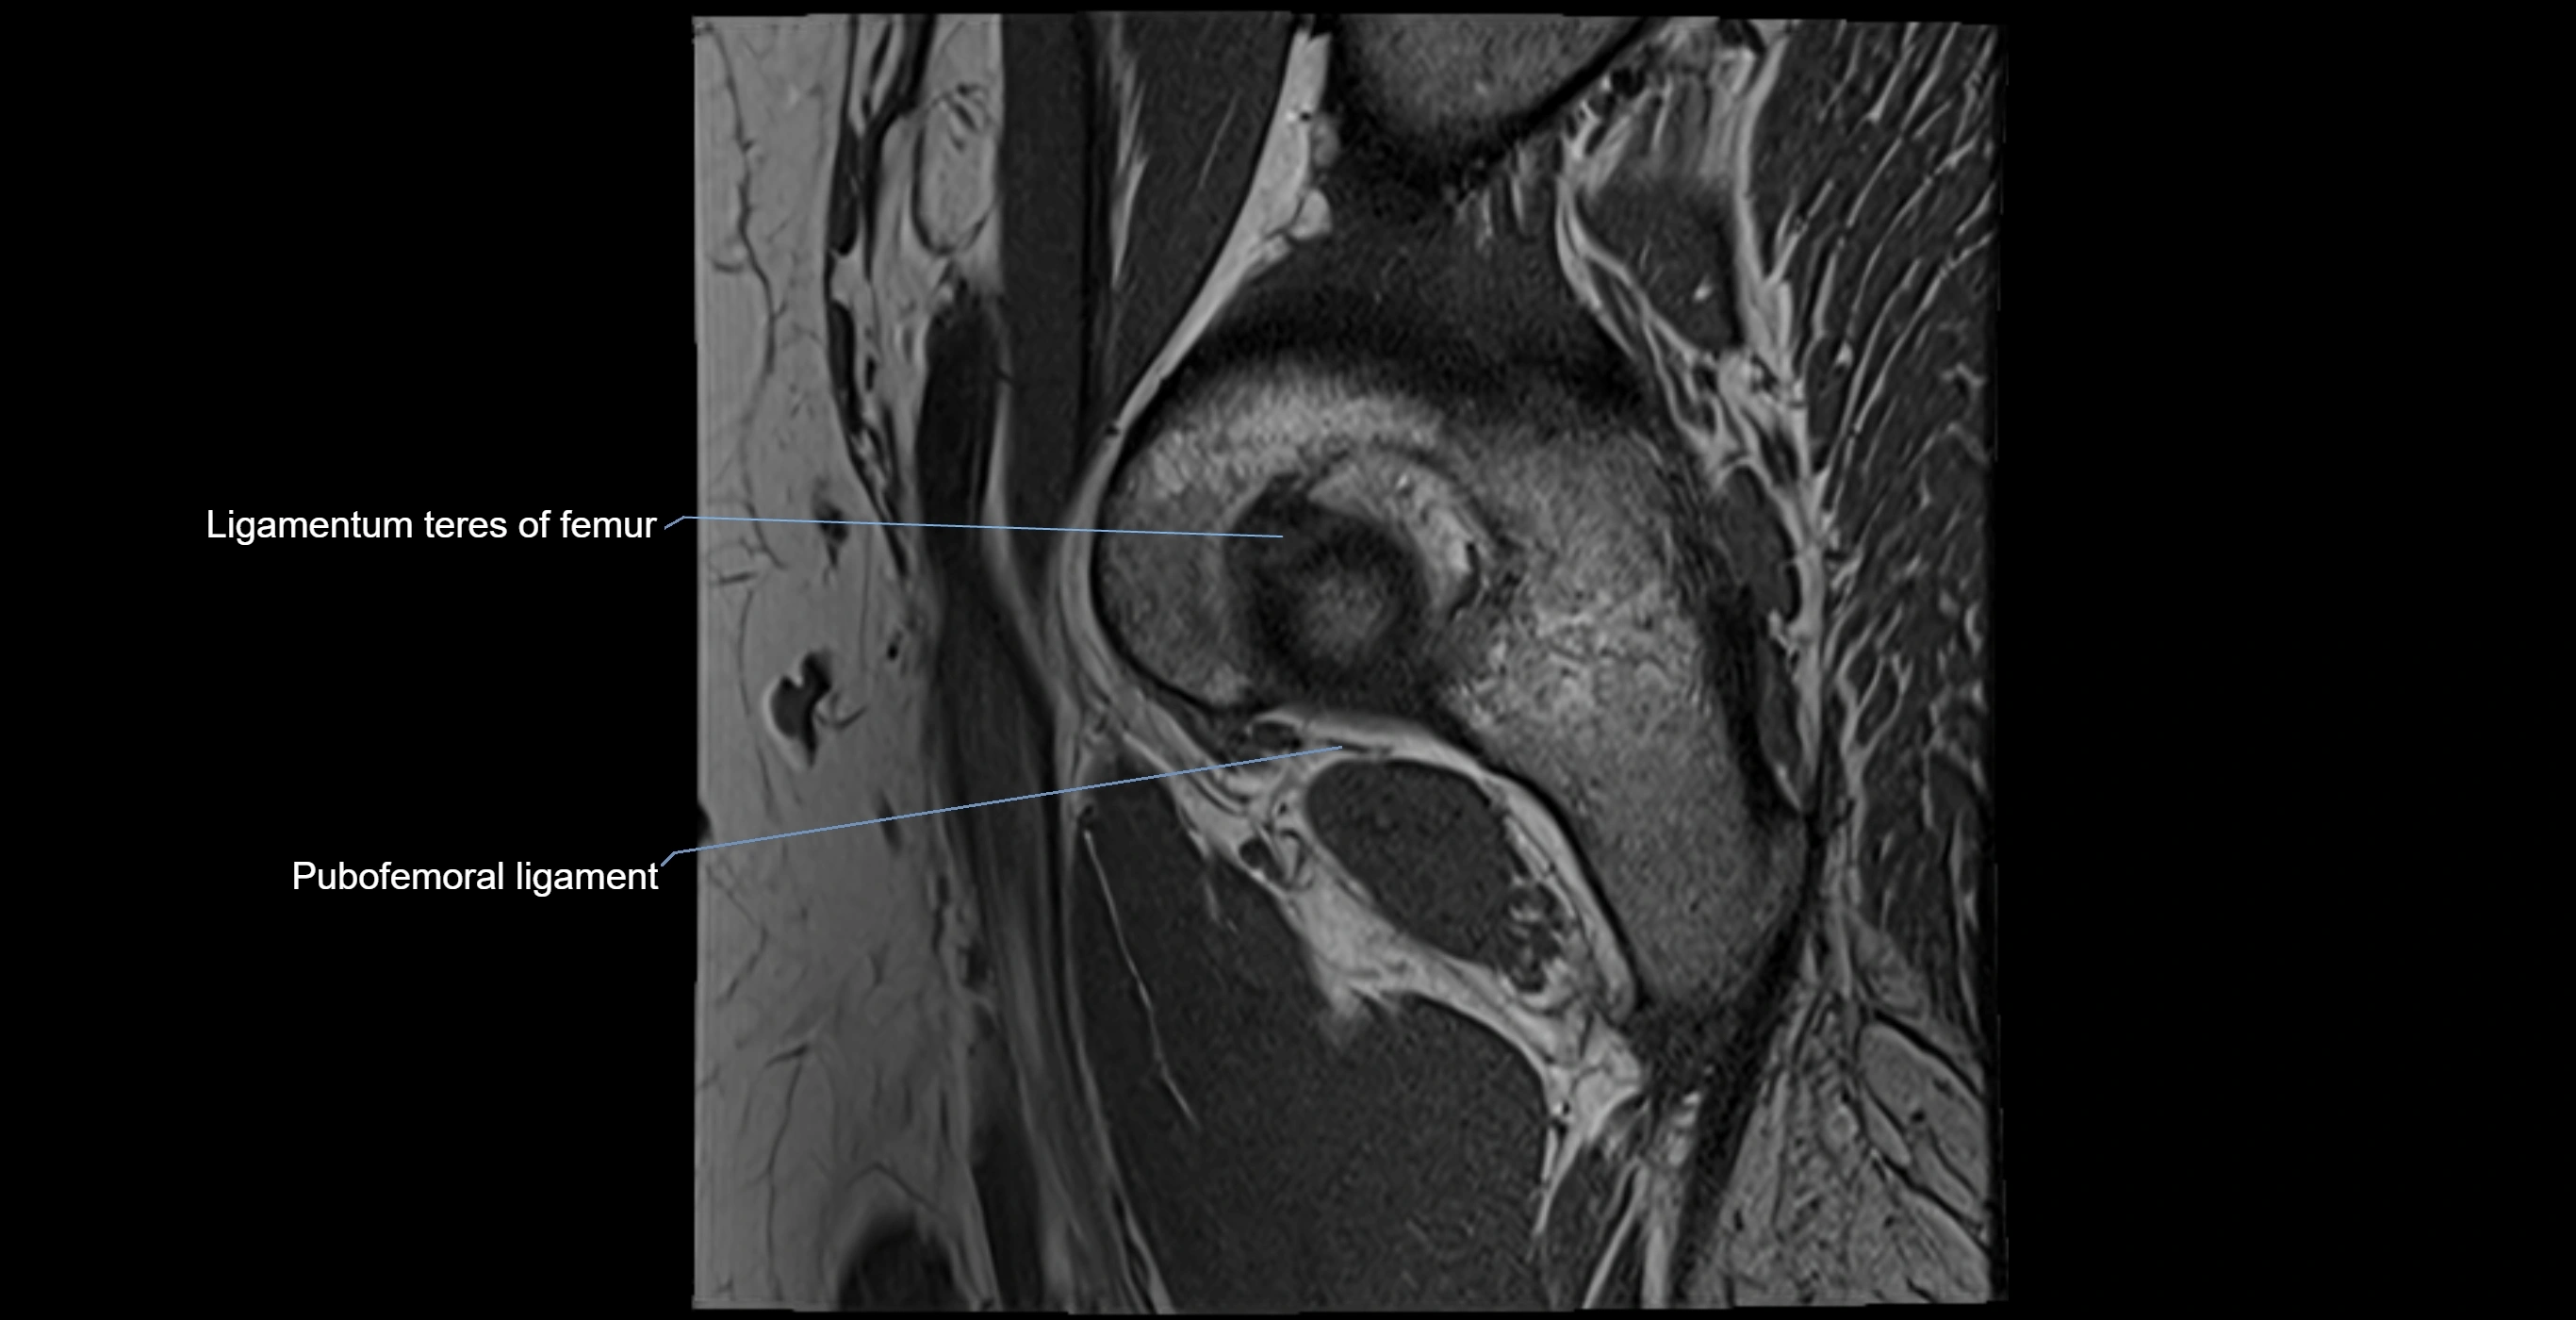

The acetabular labrum is a fibrocartilaginous ring that surrounds the rim of the acetabulum in the hip joint. It deepens the hip socket, increases joint stability, and maintains a suction seal that preserves negative intra-articular pressure. Structurally, the labrum transitions from hyaline cartilage of the acetabulum to dense fibrocartilage at its free edge.

It is triangular in cross-section, with its base attached to the acetabular rim and its apex projecting toward the femoral head. The labrum is most robust superiorly and anteriorly, where load bearing is greatest, and relatively thinner inferiorly.

Structure and Relations

• Superior and anterior labrum: thickest portions, stabilizing against anterior dislocation

• Inferior labrum: blends with the transverse acetabular ligament bridging the acetabular notch

MRI Appearance

T1-weighted images:

• Labrum: low signal intensity (dark)

• Surrounded by intermediate signal joint fluid (bright on arthrogram)

• Tears: linear or focal areas of intermediate-to-high signal interrupting labral continuity

T2-weighted images:

• Joint fluid: bright, making labral tears visible as fluid extending into or around labrum

• Degeneration: may show areas of increased signal within labrum